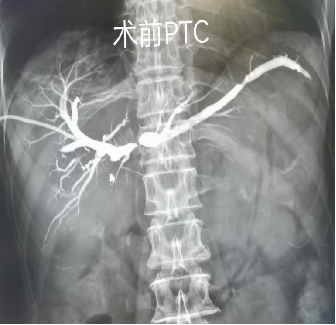

“通”即开通狭窄、闭塞、梗阻、溶解或去除血栓等,通过影像定位实现管路的精准穿刺,在影像设备的引导下精准到达罪犯血管,通过溶栓、取栓、球囊扩张、支架植入等方式完成血管狭窄的成形、闭塞的再通、血栓或栓子的取出或溶栓再通。其他自然腔道,如食管、肠道、胆道等,通过球囊扩张或支架植入等方式实现再通。

适用如下肢深静脉血栓(滤器置入+溶栓/吸栓+支架植入)、主要部位的动脉狭窄(肾动脉狭窄、锁骨下动脉狭窄、颈动脉狭窄、椎动脉狭窄、下肢动脉狭窄等的扩张成形+支架植入)、动脉慢性闭塞+急性血栓形成(急症溶栓、取栓、扩张成形、支架植入等)、空腔脏器狭窄或梗阻(食管支架、肠管支架、胆管支架植入)等疾病。